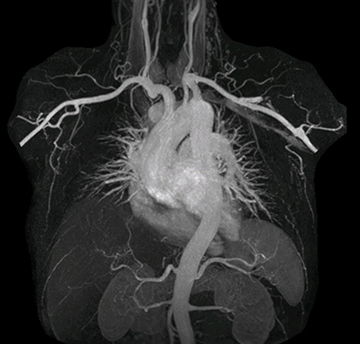

mDIXON MRA in chest

Performed on Ingenia Ambition. FOV 430 mm, voxels 1.3 x 1.3 x3.0 mm, 130 slices, Breath hold 16.6 sec